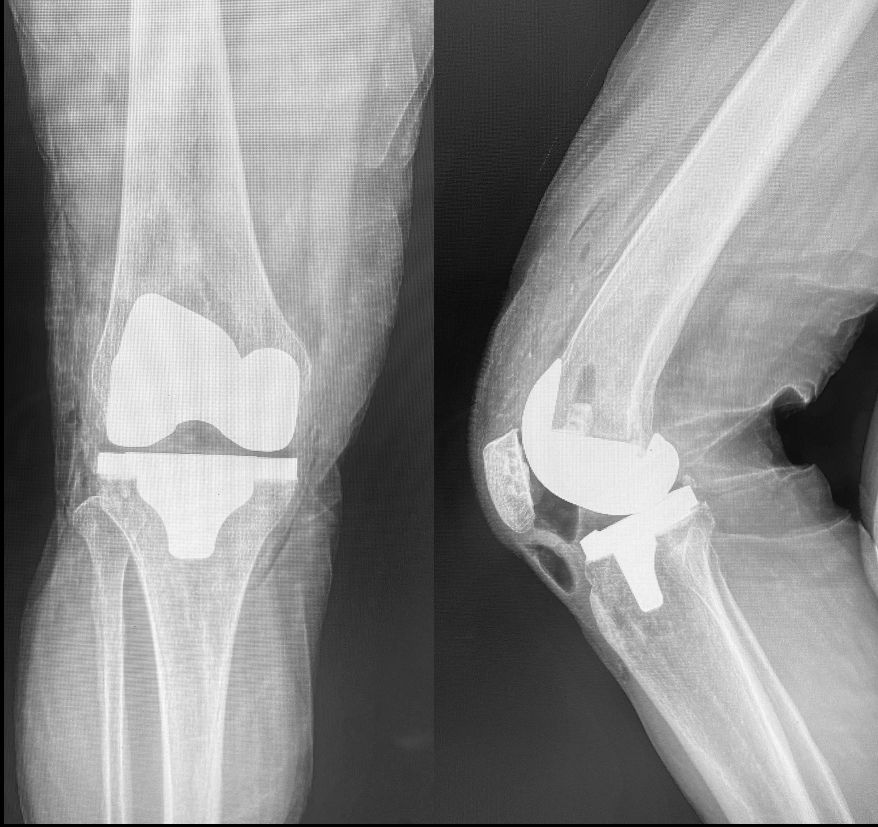

• Artrosis de rodilla

• Osteoartritis

Artroplastia de la rodilla Sin especificar